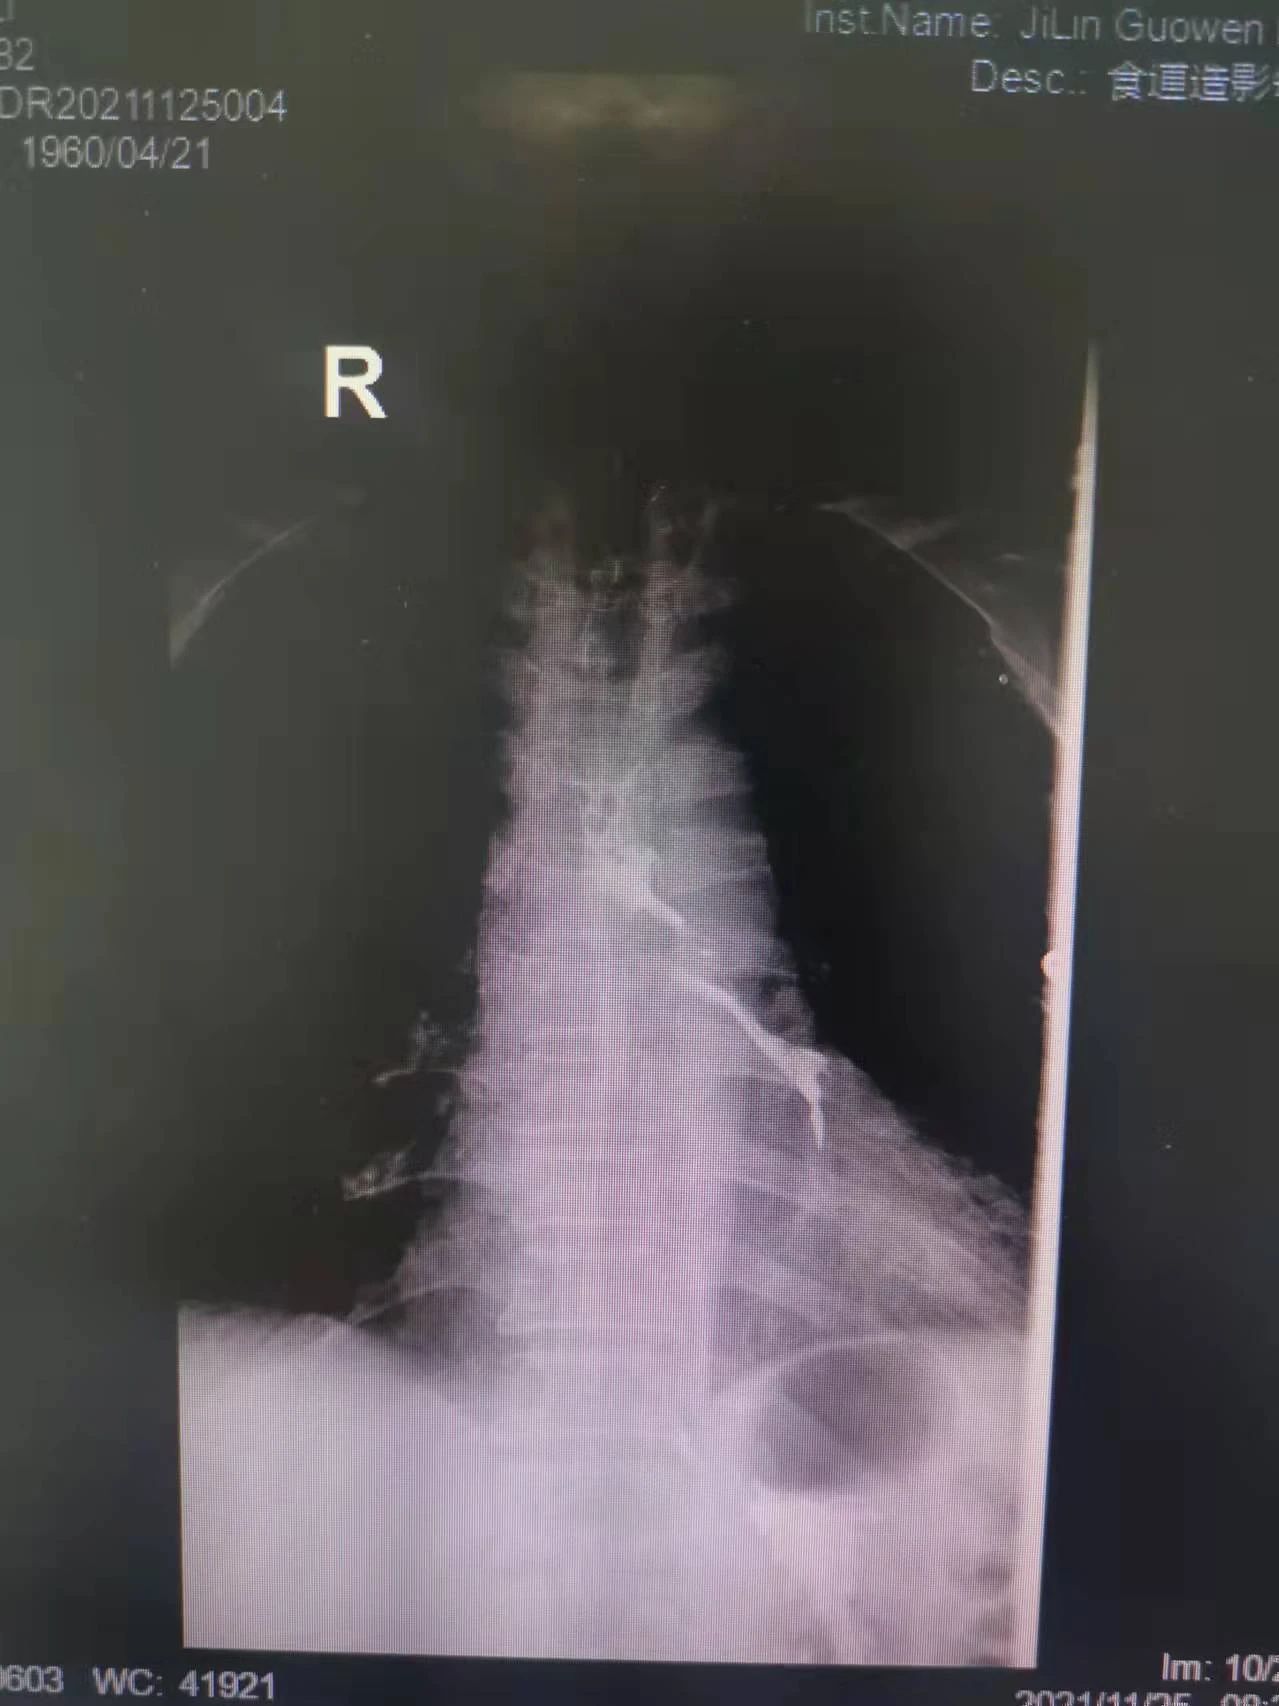

“大夫,我能喝點(diǎn)水么,我嗓子熱”今年61歲的付大爺患有食管惡性腫瘤。起初付大爺進(jìn)食時(shí)吞咽困難,每日進(jìn)食量極少,后隨著疾病的發(fā)展,付大爺進(jìn)食后伴隨劇烈嗆咳,經(jīng)系統(tǒng)檢查后,明確診斷為食管氣管瘺。為防止食物進(jìn)入氣管加重感染,付大爺聽從了醫(yī)生禁食水的意見。現(xiàn)如今,付大爺每日不光承受著癌癥所帶來的疼痛,還要承受著禁食水后仿佛置身于沙漠般的口干舌燥。這段時(shí)間里,喝一口水這么一個(gè)小小的愿望對(duì)于他來說都已成奢求!有著正常食欲卻無法進(jìn)食,可以想象對(duì)于人的生理及心理帶來多么大的創(chuàng)傷。家屬眼見付大爺痛苦不已,也是焦急萬分。

在這種情況下,我院介入二科侯主任決定通過介入治療中的食管支架植入來幫助患者實(shí)現(xiàn)這個(gè)愿望。手術(shù)當(dāng)日,侯主任在機(jī)器的幫助下,將一根細(xì)細(xì)的導(dǎo)絲穿過腫瘤到達(dá)付大爺胃部,然后再沿著導(dǎo)絲,把壓縮好的支架放在腫瘤里面。通過后撤導(dǎo)管,把壓縮的支架打開,支架把腫瘤撐開,讓食管不再堵塞。有了支架的支撐,付大爺就可以自由地吃東西了,哪怕食管和氣管有溝通,因?yàn)橹Ъ芨采w了腫瘤,通道堵住了,吃的東西也不會(huì)吸到肺內(nèi)造成感染。這時(shí)痛痛快快地吃上一頓,也不再是奢望!